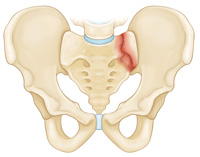

Lateral compression fracture. In this fracture, the pelvis is pushed inward.

Stable fracture. In this type of fracture, there is often only one break in the pelvic ring and the broken ends of the bones line up adequately. Low-energy fractures are often stable fractures. Stable pelvic fracture patterns include: